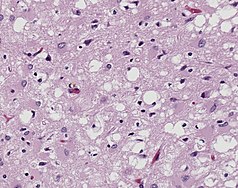

Prions are misfolded proteins that are transmissible and can influence abnormal folding of normal proteins in the brain. They do not contain any DNA or RNA and cannot replicate other than to convert already existing normal proteins to the misfolded state. These abnormally folded proteins are found characteristically in many neurodegenerative diseases as they aggregate the central nervous system and create plaques that damages the tissue structure. This essentially creates "holes" in the tissue. It has been found that prions transmit three ways: obtained, familial, and sporadic. It has also been found that plants play the role of vector for prions. There are eight different diseases that affect mammals that are caused by prions such as scrapie, bovine spongiform encephalopathy (mad cow disease) and feline spongiform encephalopathy (FSE). There are also ten diseases that affect humans, such as Creutzfeldt–Jakob disease (CJD)[19] and Fatal familial insomnia (FFI).[citation needed]